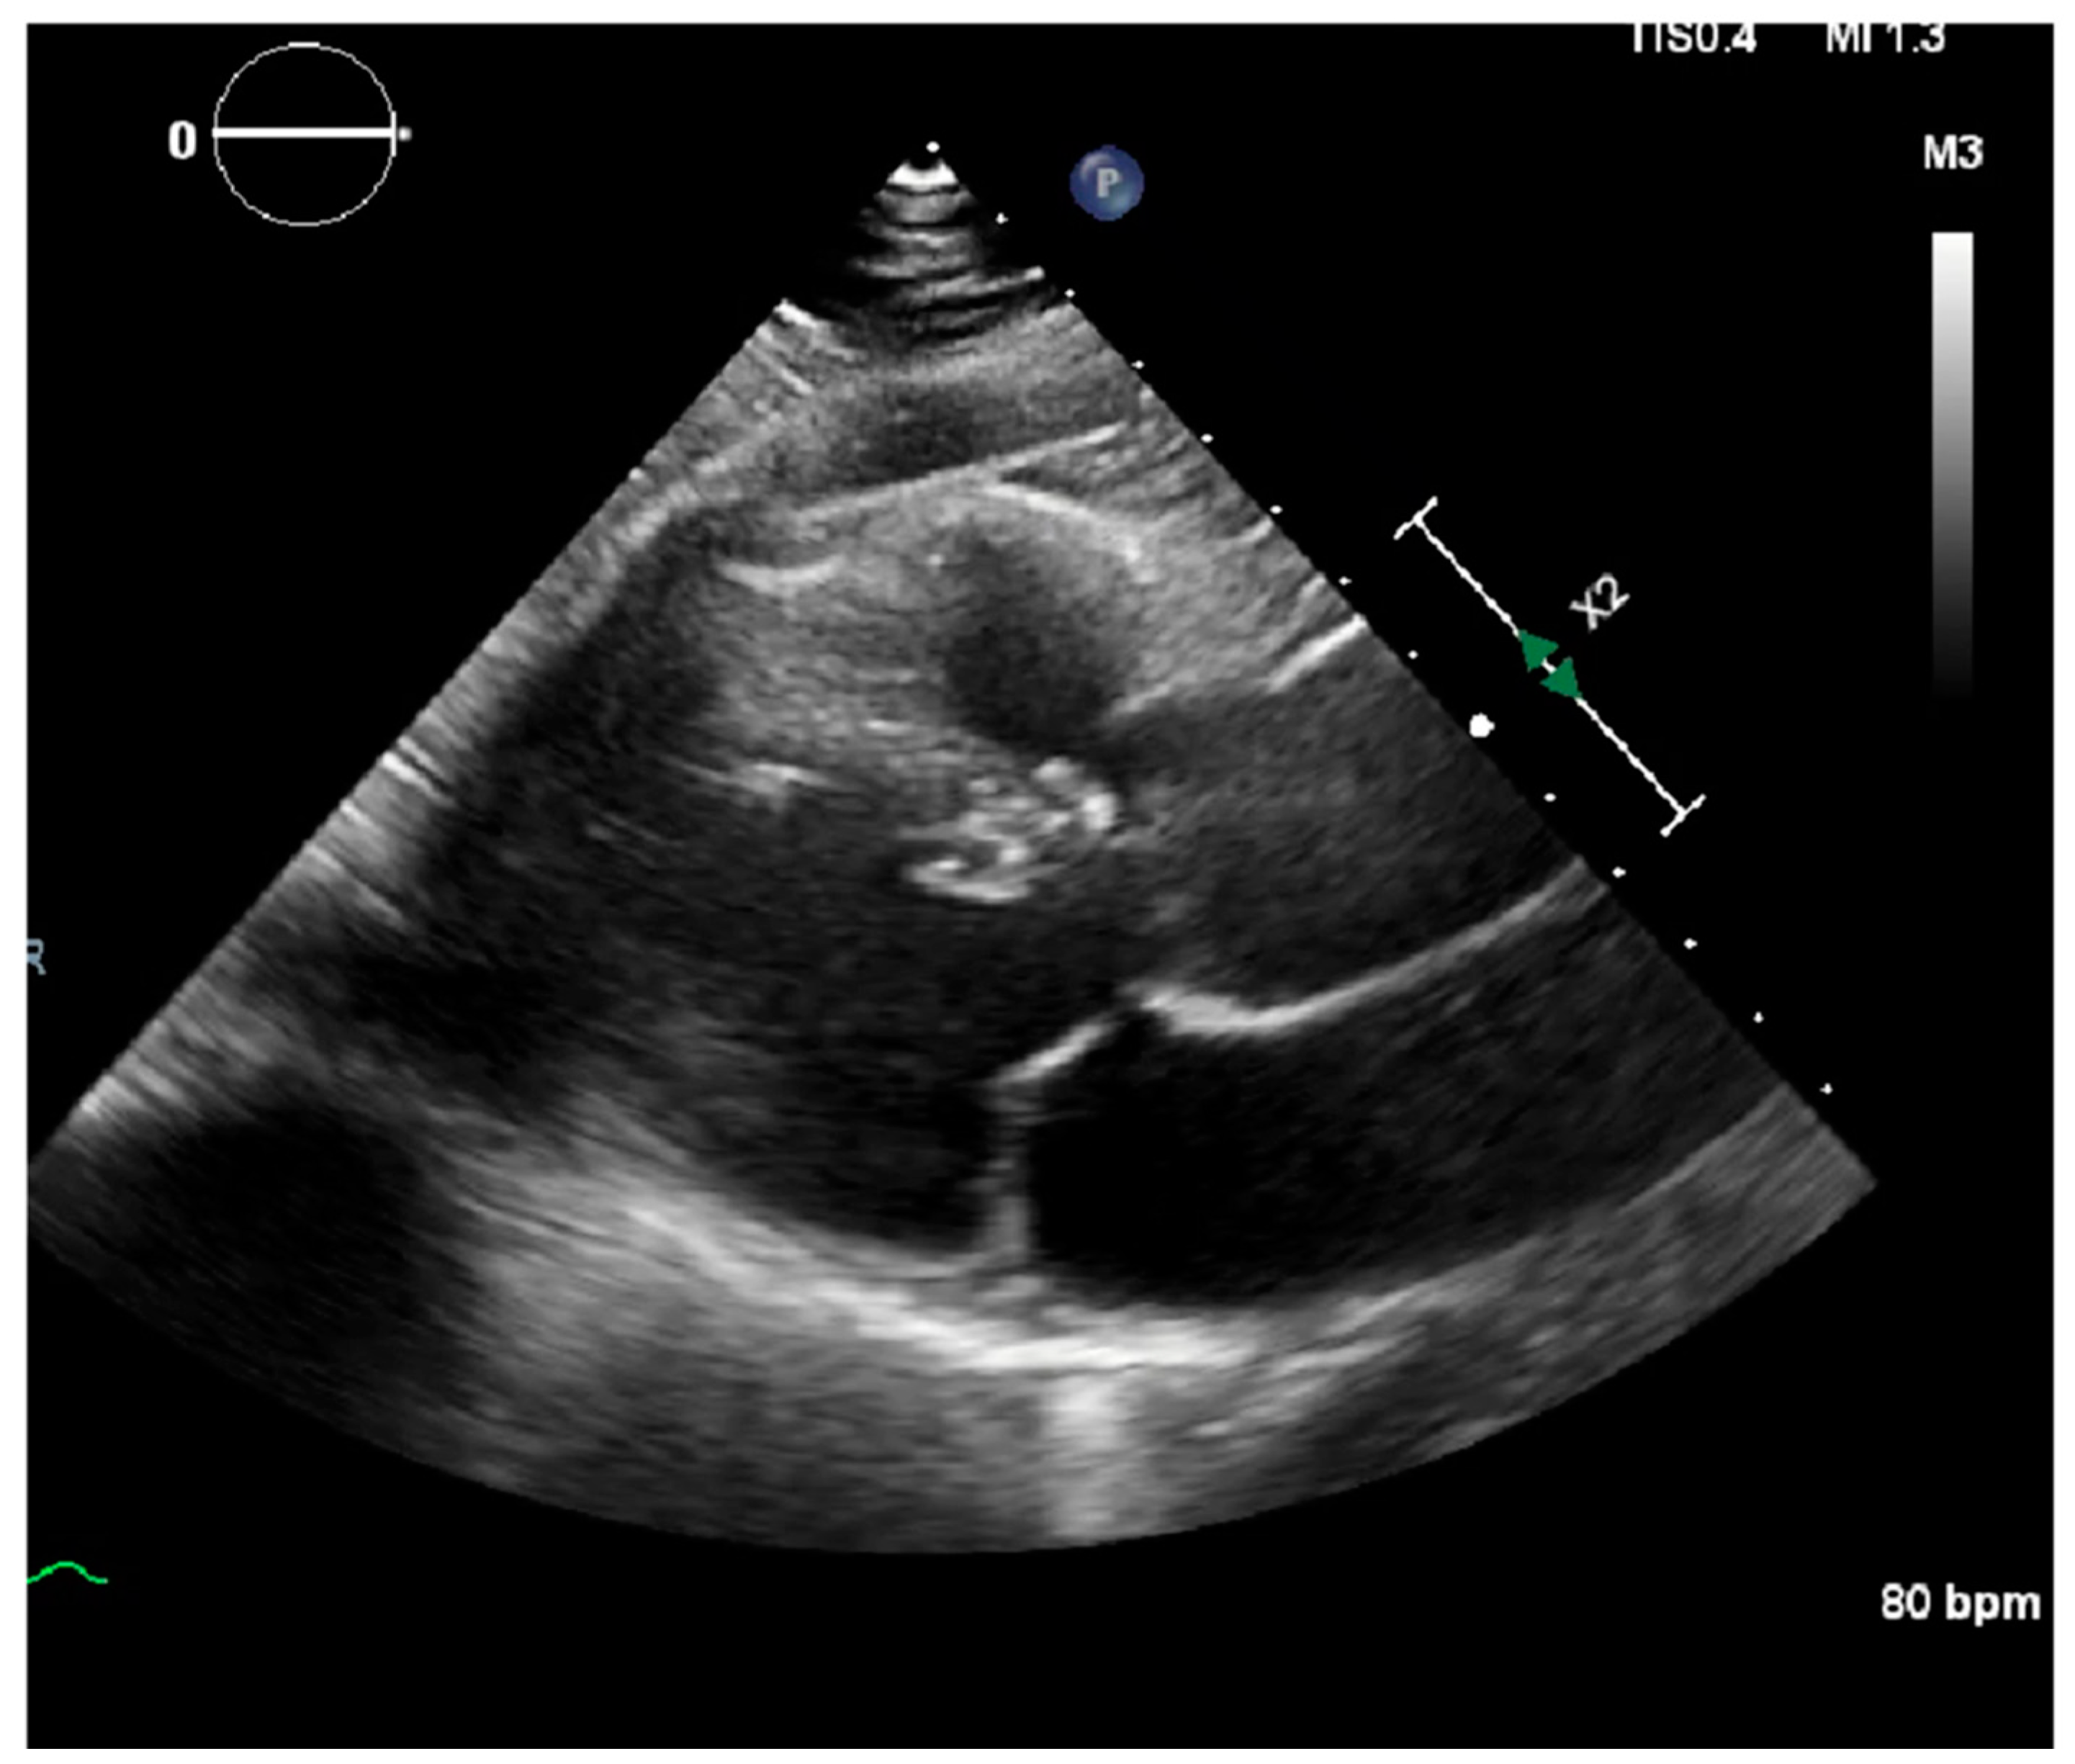

Laboratory results were as follows: WBC 8.64 K/uL (3.60–9.50), creatinine 0.8 mg/dL (0.4–1.0), TSH 1.69 uIU/mL (0.34–5.60), troponin < 0.03 ng/mL (≤0.4), D-dimer 387 ng/mL (<670), BNP < 10 pg/mL (≤106), CRP < 5.00 mg/L (≤10.00), procalcitonin 0.04 ng/mL (0.00–0.10); urine analysis negative; COVID-19 PCR infection negative; chest X-ray with no acute findings; echocardiograph with grade I diastolic dysfunction; and EF 60–65% (Figure 1 and Figure 2). EKG showed sinus tachycardia with a heart rate of 101 bpm (Figure 3). Lung CTA was observed with no significant lung pathology, and the pulmonary function test was within normal limits.

Figure 2. Echocardiography showing mitral valve and left ventricle with no pericardial effusion.